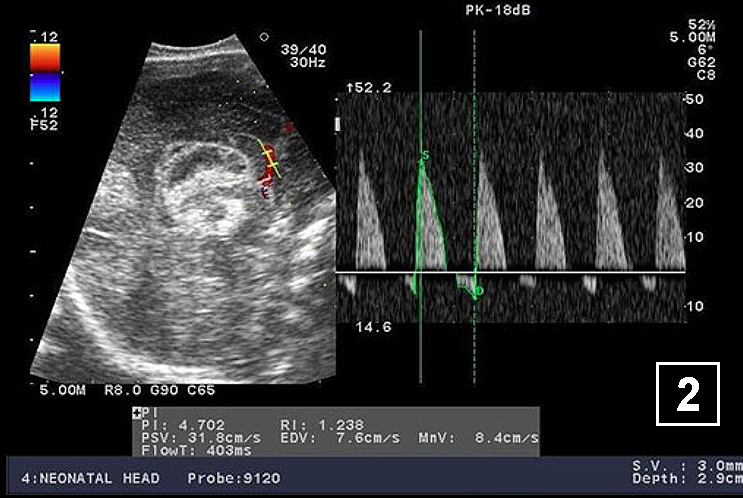

Neonatology Hydrocephalus Doppler 2 Image